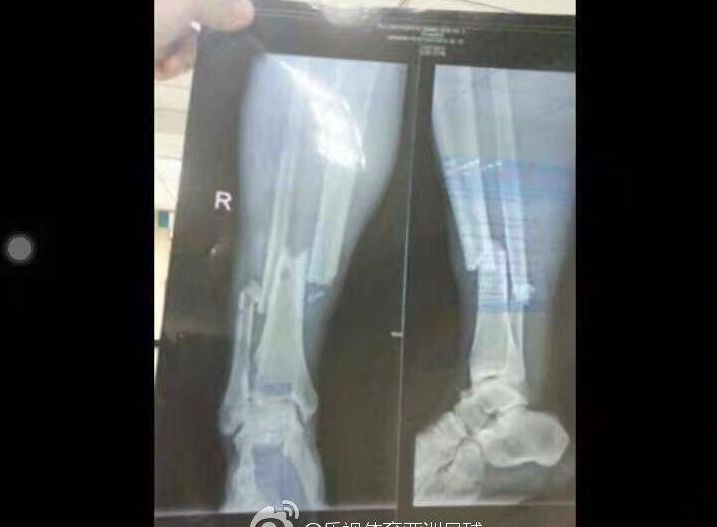

В китайских СМИ появились фотографии рентгена ноги Демба Ба, сломавшего ногу

В китайских СМИ появились фотографии рентгена ноги нападающего "Шанхай Шэньхуа" Демба Ба после травмы, полученной в матче 17-го тура китайской суперлиги против "Шанхай Шанган". Во втором тайме экс-форвард "Челси" столкнулся с соперником, неудачно поставил ногу на газон и заработал перелом.